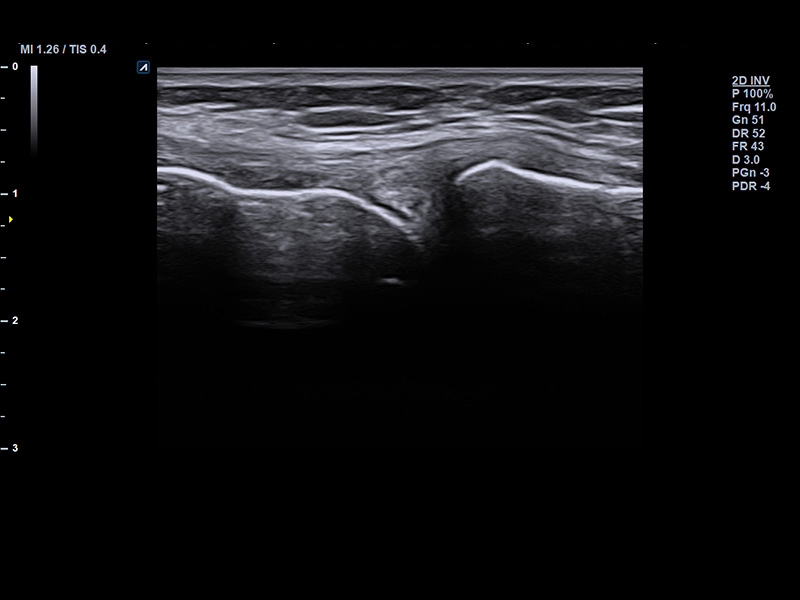

L3-8H

High density low frequency linear transducer (3-8MHz)

Application:

Breast, EM, MSK, Vascular, Small Parts